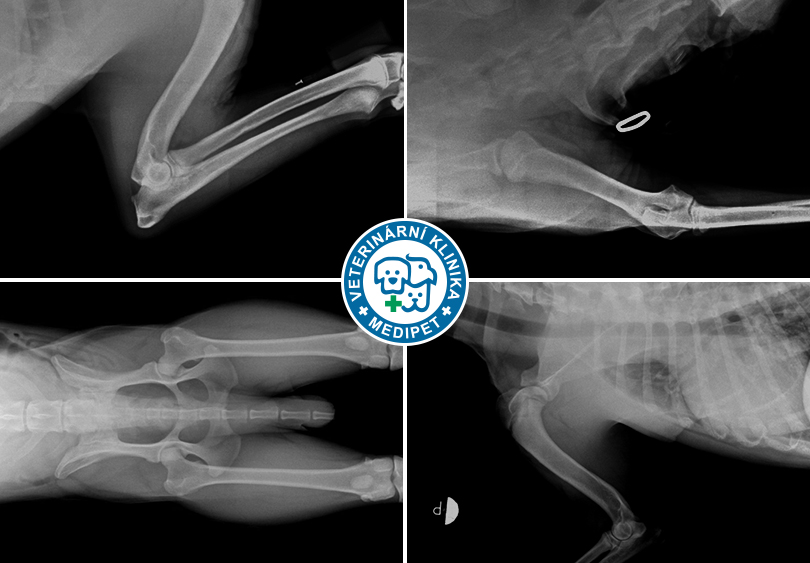

RTG Dysplazie loketního kloubu (DLK)